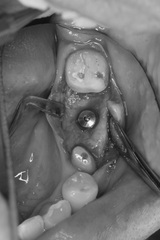

写真はインプラント埋入術前。左下第一大臼歯欠損です。

CT撮影を行い、インプラント埋入位置や方向を計画。

骨量は十分で、特に骨造成の必要もありませんでした。

術前の計画に基づきインプラント埋入。